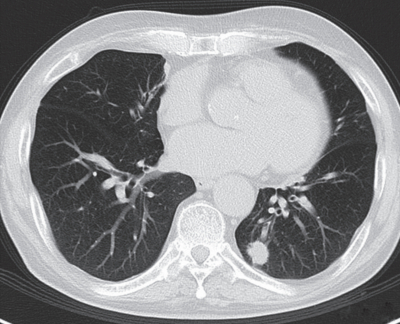

79歳の男性。肺がん検診で胸部異常陰影を指摘され来院した。昨年の検診では異常は指摘されず、自覚症状はない。精査の結果、臨床病期IA期の左下葉肺腺癌と診断された。最大腫瘍径は2.0cmであった。本人の希望で放射線治療を行うこととした。胸部CTを別に示す。